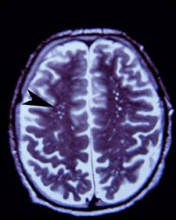

“frontal lobes(额叶,也叫大脑前庭)萎缩。”Fayed(法耶德)指着一张核磁共振成像扫描图片图片上的脑部黑白截面说。掌控高级神经功能的The frontal cortex(前额叶)正好位于前额后面,它的样子仿佛一片干果。这种损伤导致病人的计划能力,集中注意力的能力以及在复合决策能力受损。这是一种永久性的损伤。

图片说明:增大了的VR空间-更常见于老年人中-从这个年轻的业余登山者从阿空加瓜山返回后拍摄的脑部扫描图中明显可见。